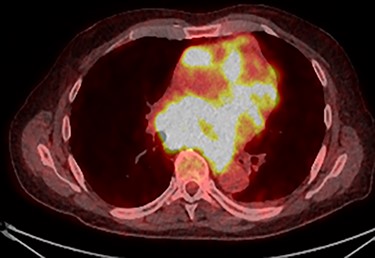

PET scan (transverse plane) demonstrating an enhancing lesion encroaching the heart with necrotic lymph nodes.